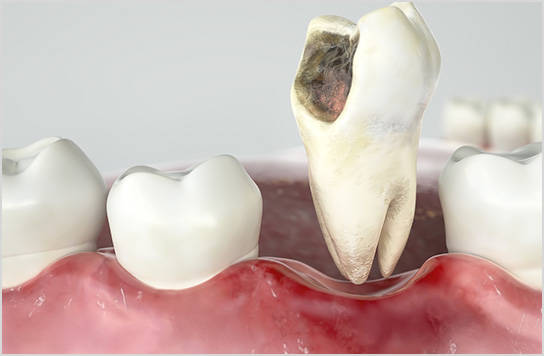

■精密な虫歯治療

詰め物の中が虫歯になっていた。セラミック素材で再治療を行ったケース。

神奈川県川崎市の武蔵小杉駅1分の歯医者、岡野歯科医院。当医院で行っているマイクロスコープ(歯科用顕微鏡)を用いた歯科治療(根管治療・歯周病治療・虫歯治療)は、通常の保険内の歯科治療とは、その精密さや、成功率において全く違う治療とお考え下さい。

最近では、歯科用顕微鏡を導入した医院も増え、一部保険内で顕微鏡治療を行っている医院もあるかもしれませんが、実際は低倍率のまま治療をしているところも少なくありません。当医院では、しかるべき材料を使い、高倍率で患部を視認し、しっかりと時間をかけて高精度の根管治療、被せ物治療を行っています。結果、長い目でみたときにインプラント、義歯(入れ歯)にならないよう、口腔環境を改善・維持することが可能になるのです。すべては、再発を防ぎ、患者さんがこれから先、末永くご自身の歯を使っていただくための治療です。